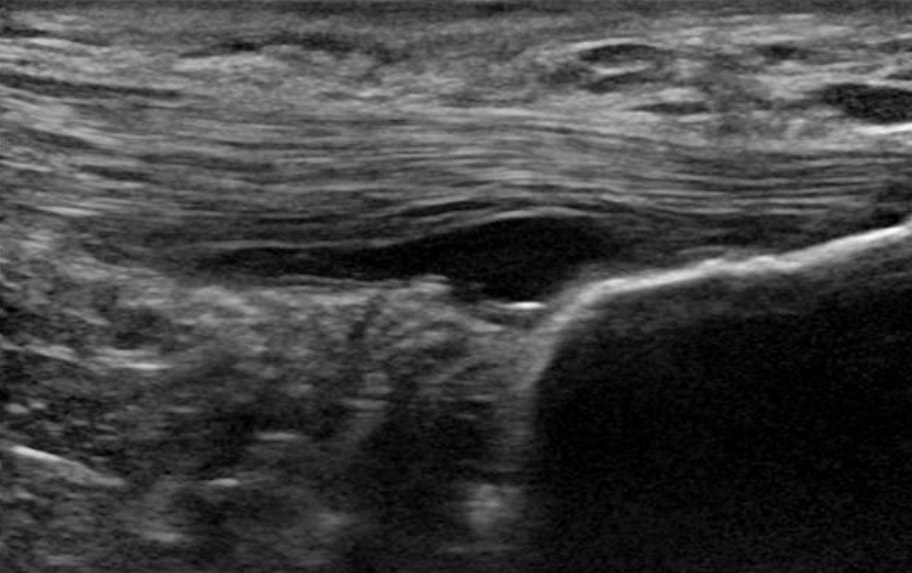

1. Nie je známy nociceptívny faktor bolesti v šľachách. Patológia viditeľná na zobrazovacom zariadení nie je príčinou bolesti. Cievnatosť nie je zdrojom bolesti, je len ukazovateľom degenerácie šliach. Okrem toho sa v šľache nenachádzajú žiadne senzorické nervy, ale na periférii okolo šľachy. Nervy, ktoré prerastajú do patologickej šľachy, sú sympatické nervy, nie senzorické. Napokon, centrálna senzibilizácia je pravdepodobne menším problémom pri patológii dolných končatín v porovnaní s patológiou horných končatín(Plinsinga et al. 2015, Plinsinga et al. 2018).